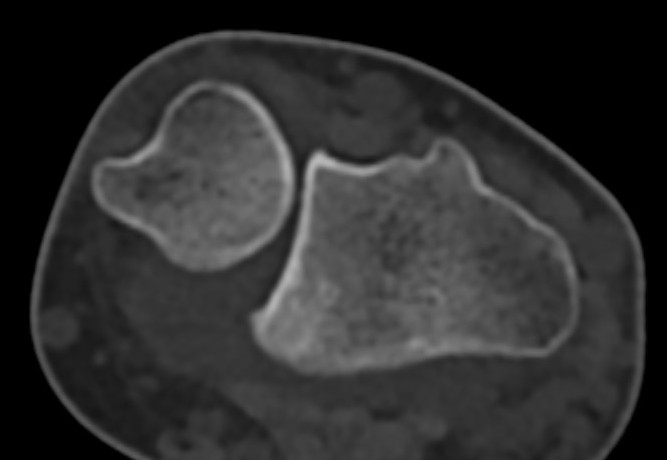

CT

Dorsal subluxation of the distal ulna